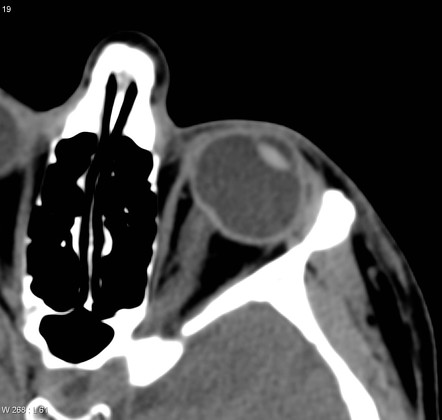

시신경유두는 산동검사를 하면서 망막의 시신경을 관찰하게되면,

시신경유두는 약간 볼록한 모양을하고 있습니다.

그래서 이름을 시신경유두라고 불리며, 영어로는 Papilla, Optic disc 혹은 Optic nerve head 라고합니다.

시신경유두는 망막의 신경절세포(Retinal ganglion cell)의 축삭(Axon)이 모여서,

망막신경섬유(Retinal nerve fiber)가 되어서 이들이모여서,

안구를 빠져나가는 부위, 출구에 해당하는 부분입니다.

시신경유두에는 망막과, 이를둘러싸고 있는 맥락막, 가장 바깥쪽의 공막이 모두 모여있는 부위입니다.

가장 표면에 있는 부분이 바로 망막에 해당하는 부분이며, 수평으로 주해하던 망막신경섬유들이 안구 바깥을 향해 90도로 회전하게 됩니다.

안구를 빠져나가려고하는 망막신경섬유층(RNFL)이 시신경유두 전체부피의 90%를 차지 하게됩니다.